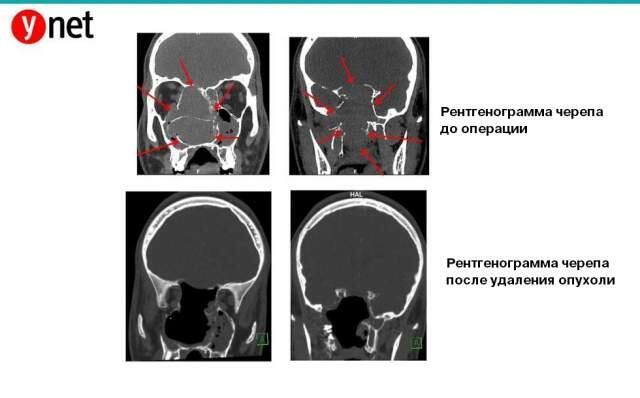

Там сделали снимок черепа и установили причину кровотечений. Ею оказалась 7-сантиметровая опухоль в полости носа. Она заполнила носовую полость и синусы, распространилась на нижнюю челюсть и оказывала давление на глаза и мозг.

По этой причине операцию провели в несколько этапов. На первом этапе д-р Амсалем провел больному сложную катетеризацию (цинтур) сосудов головы. В ходе процедуры выявили сосуды, снабжающие кровью опухоль, и закупорили их биологическим клеем. Это позволило предотвратить массивное кровотечение.

Лишь после этого ЛОР-врач Ури Пелег вместе с нейрохирургом Лиором Гоненом удалили опухоль через ноздри.